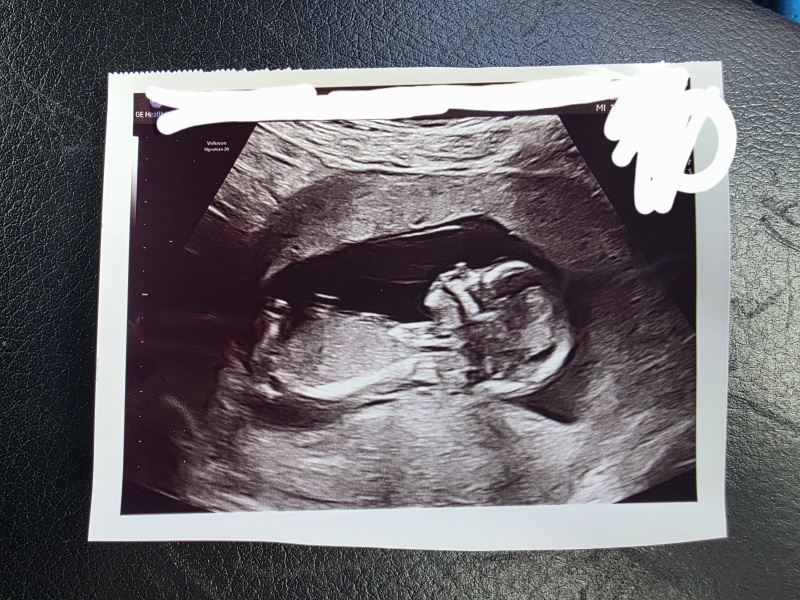

I had a 10 weeks scan and this was the potty shot I received. Just curious whether people think boy or girl from this scan photo?